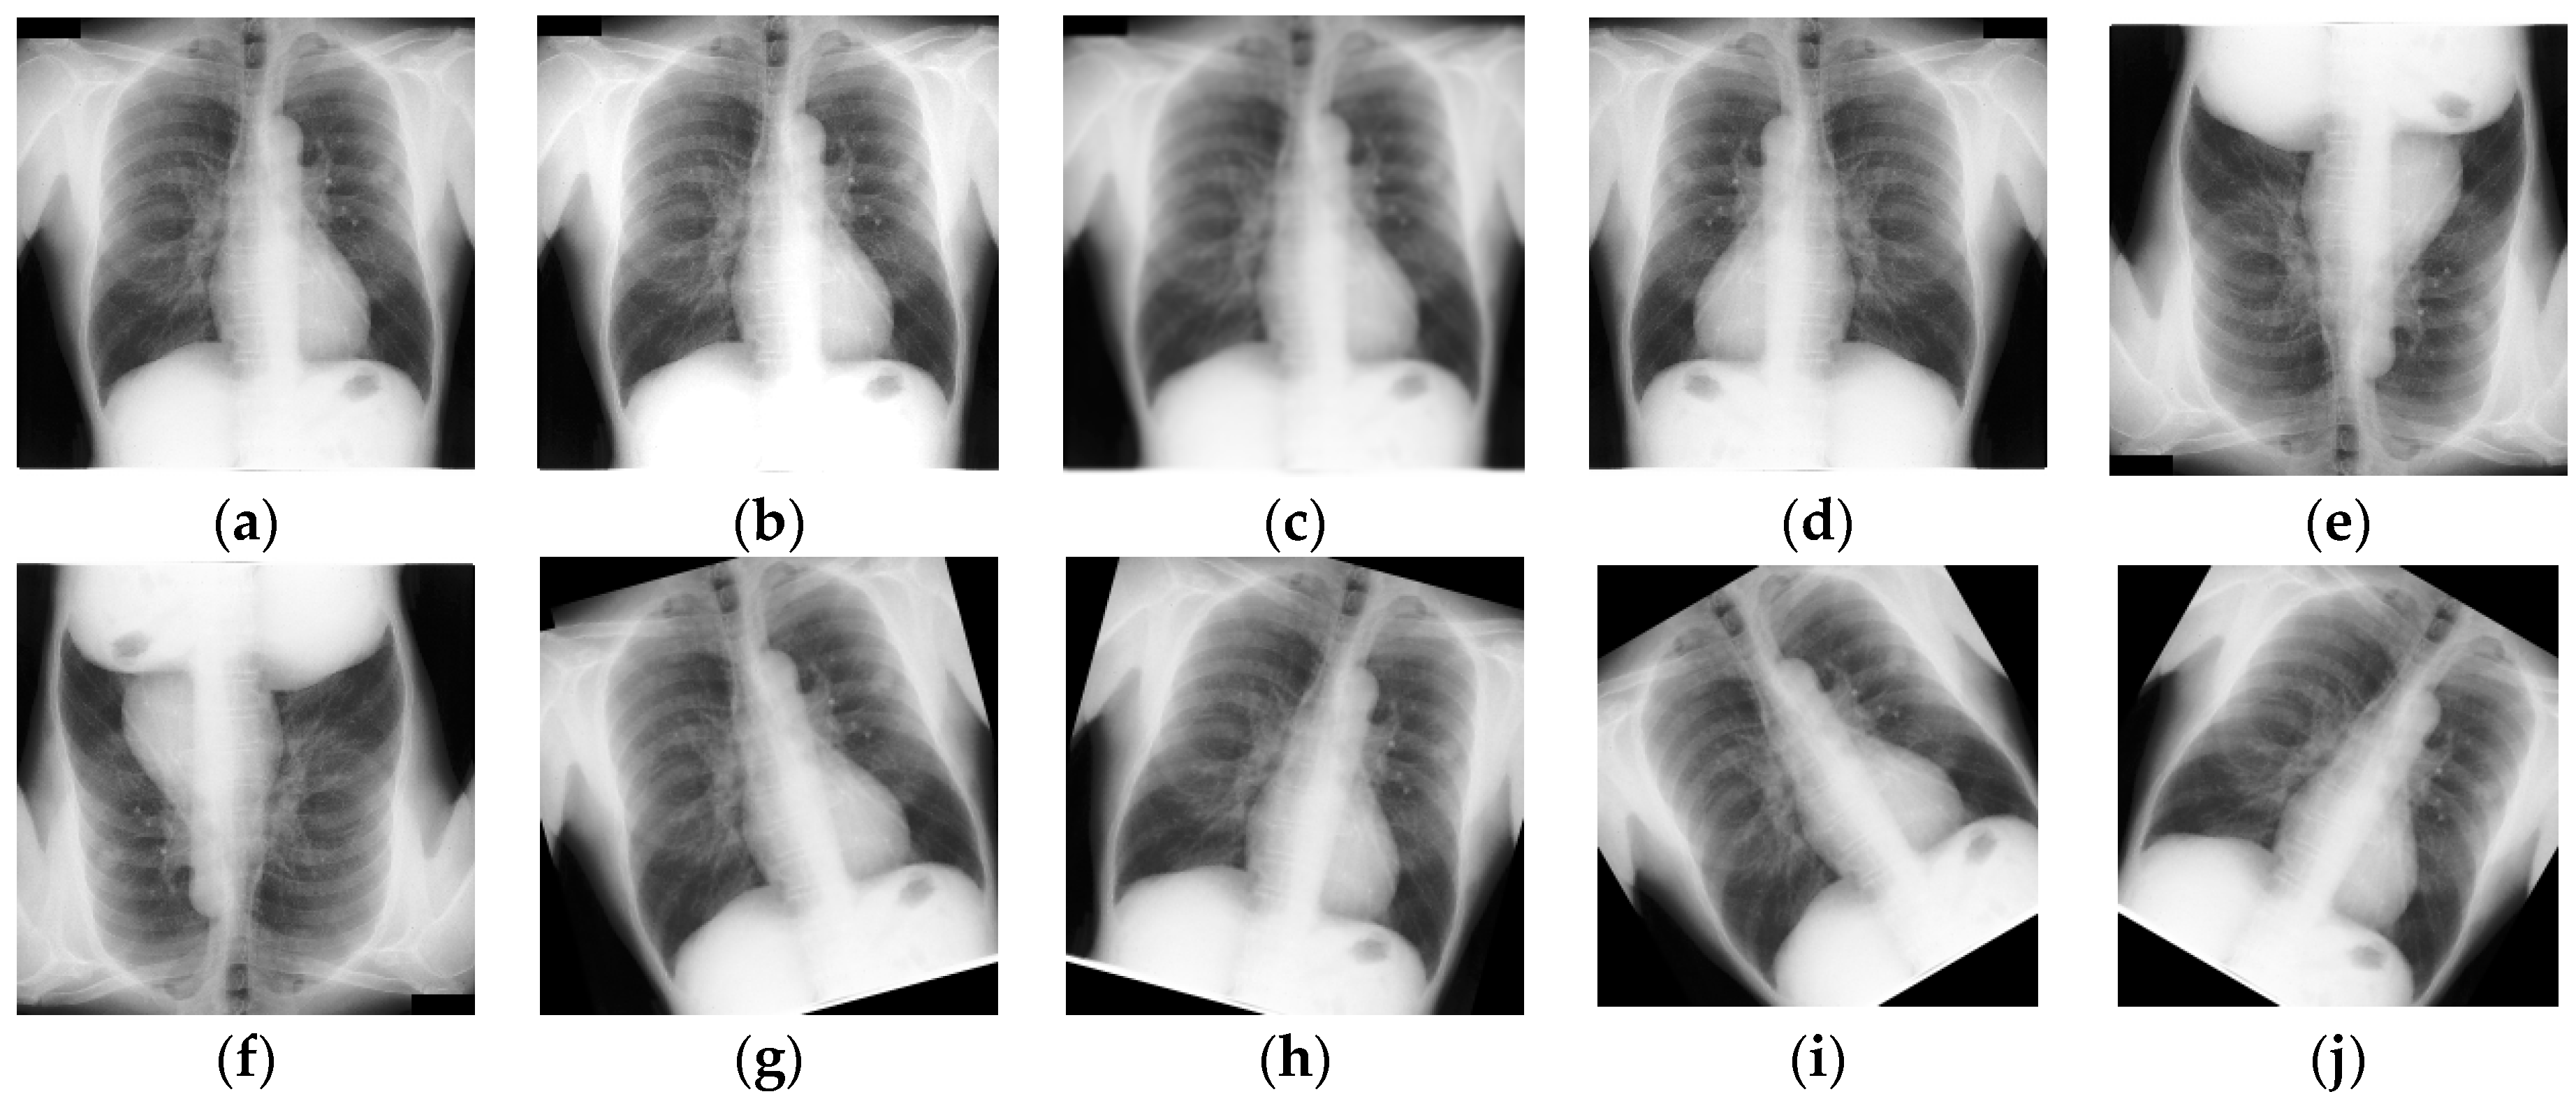

3.1. Dataset Description

3.2. Data Preprocessing and Augmentation